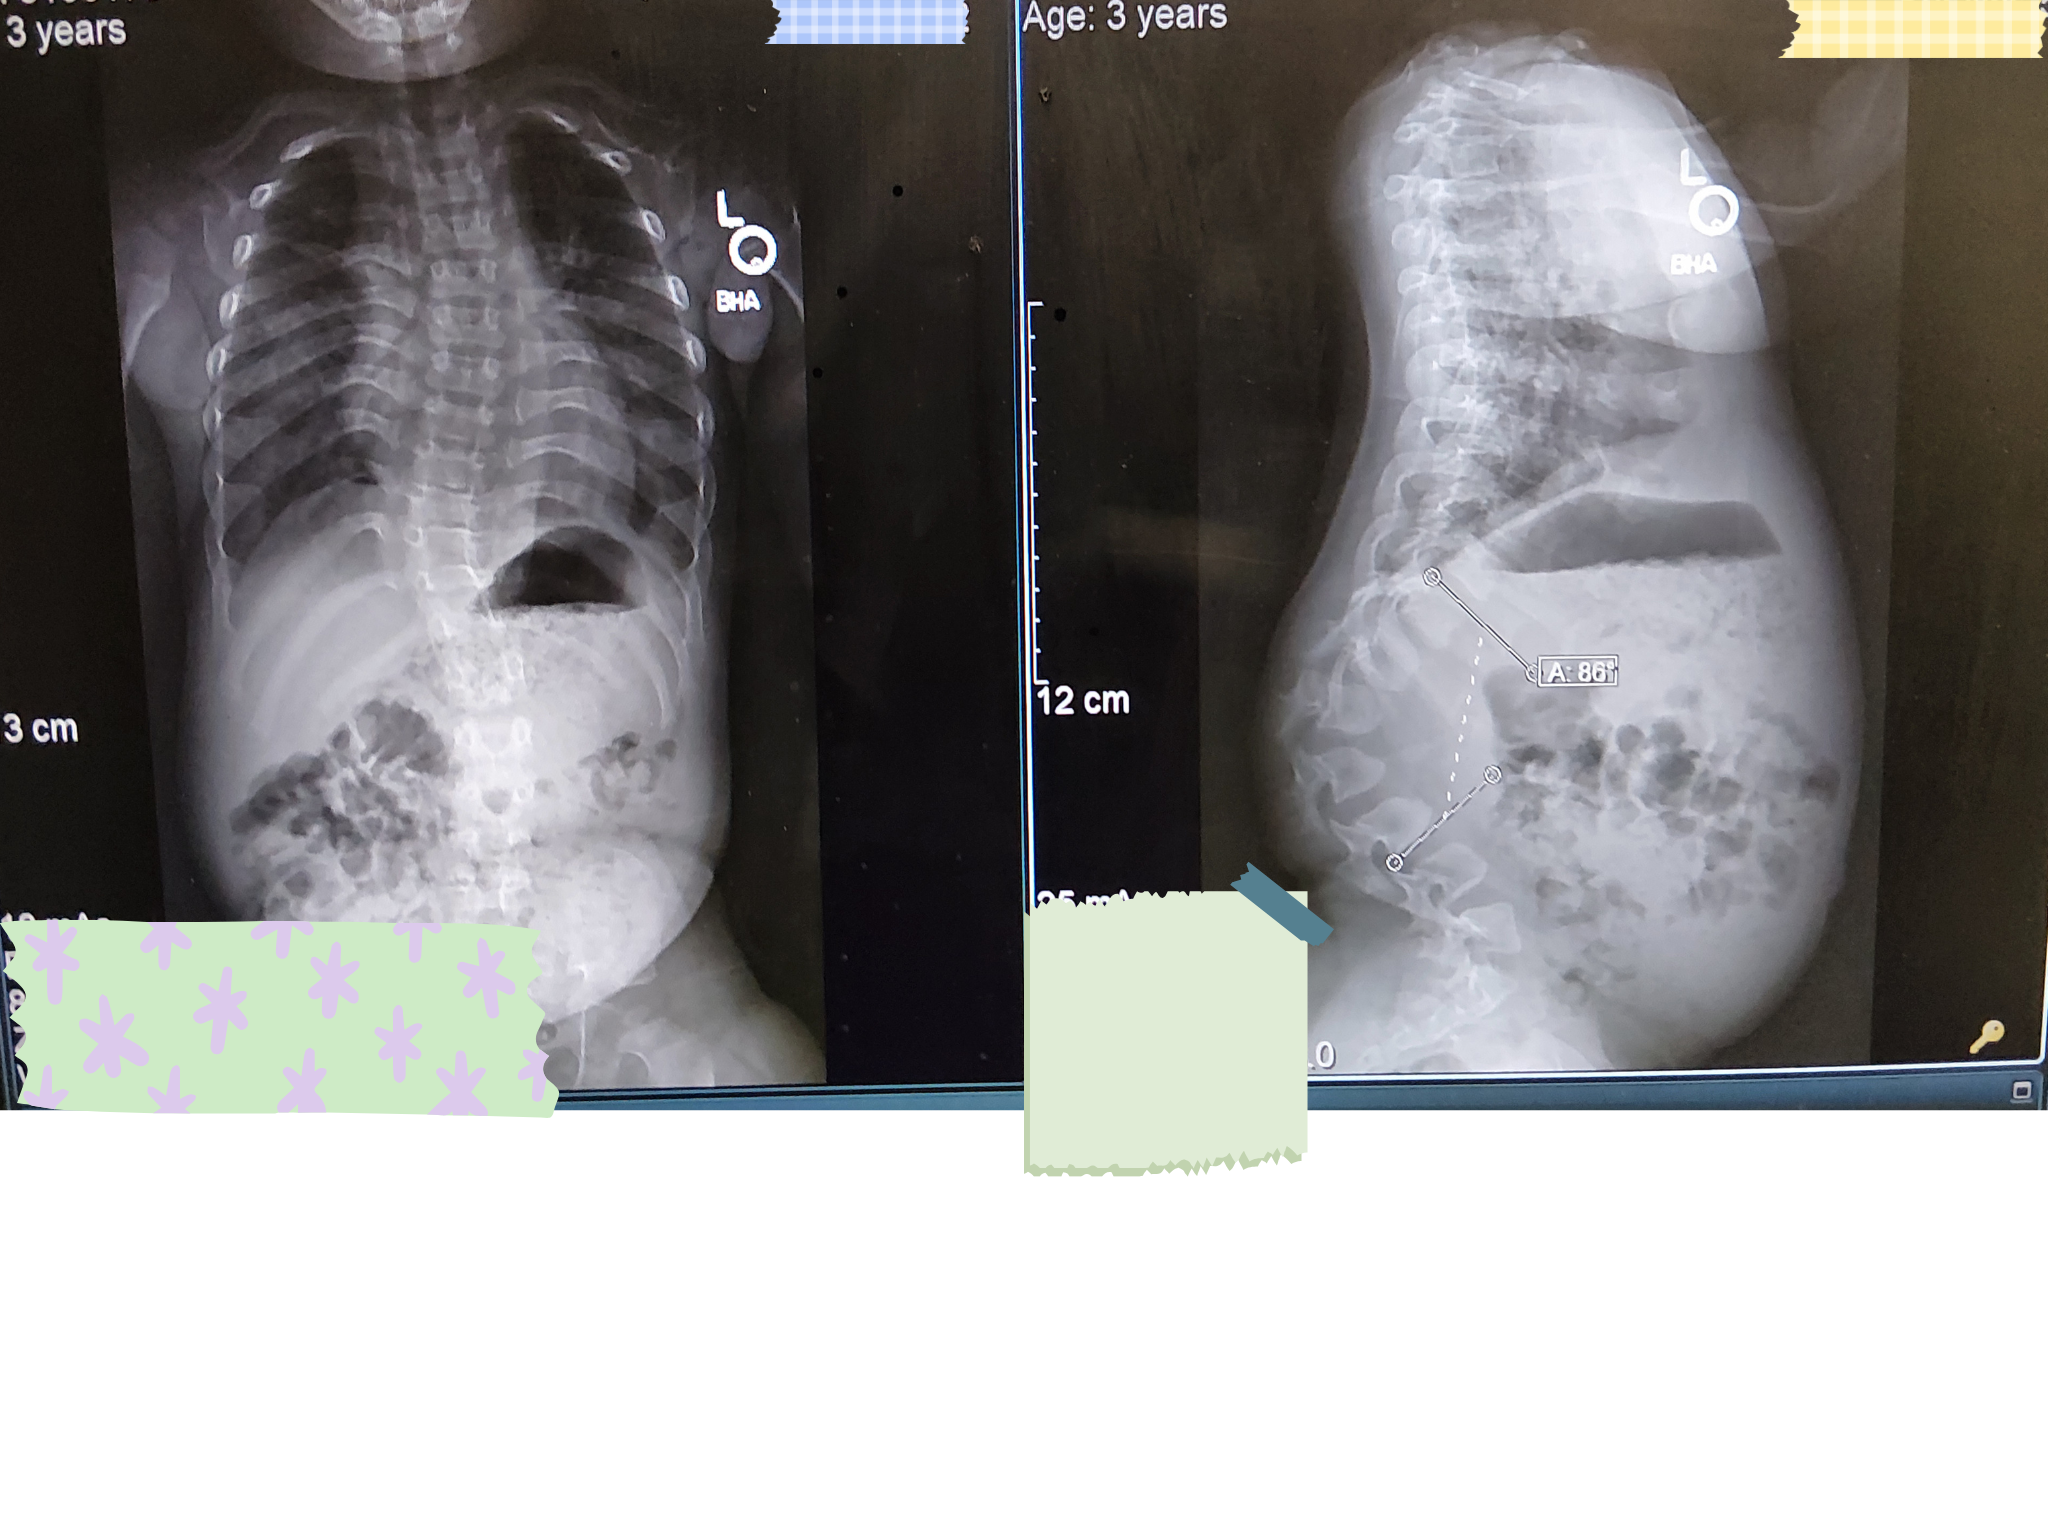

Achondroplasia is a rare condition, but he is also facing an even rarer challenge: severe spinal kyphosis (curvature of the spine). This complication is very uncommon even among those with his condition. Since his diagnosis, he has already braved three surgeries and respiratory issues, showing everyone how strong he can be.

The road ahead is filled with numerous medical appointments and a potential major spinal surgery, followed by a long recovery period. Because these treatments require extensive travel and long-term specialized care, the expenses beyond direct medical fees, such as travel, lodging, and specialized therapy are becoming substantial.